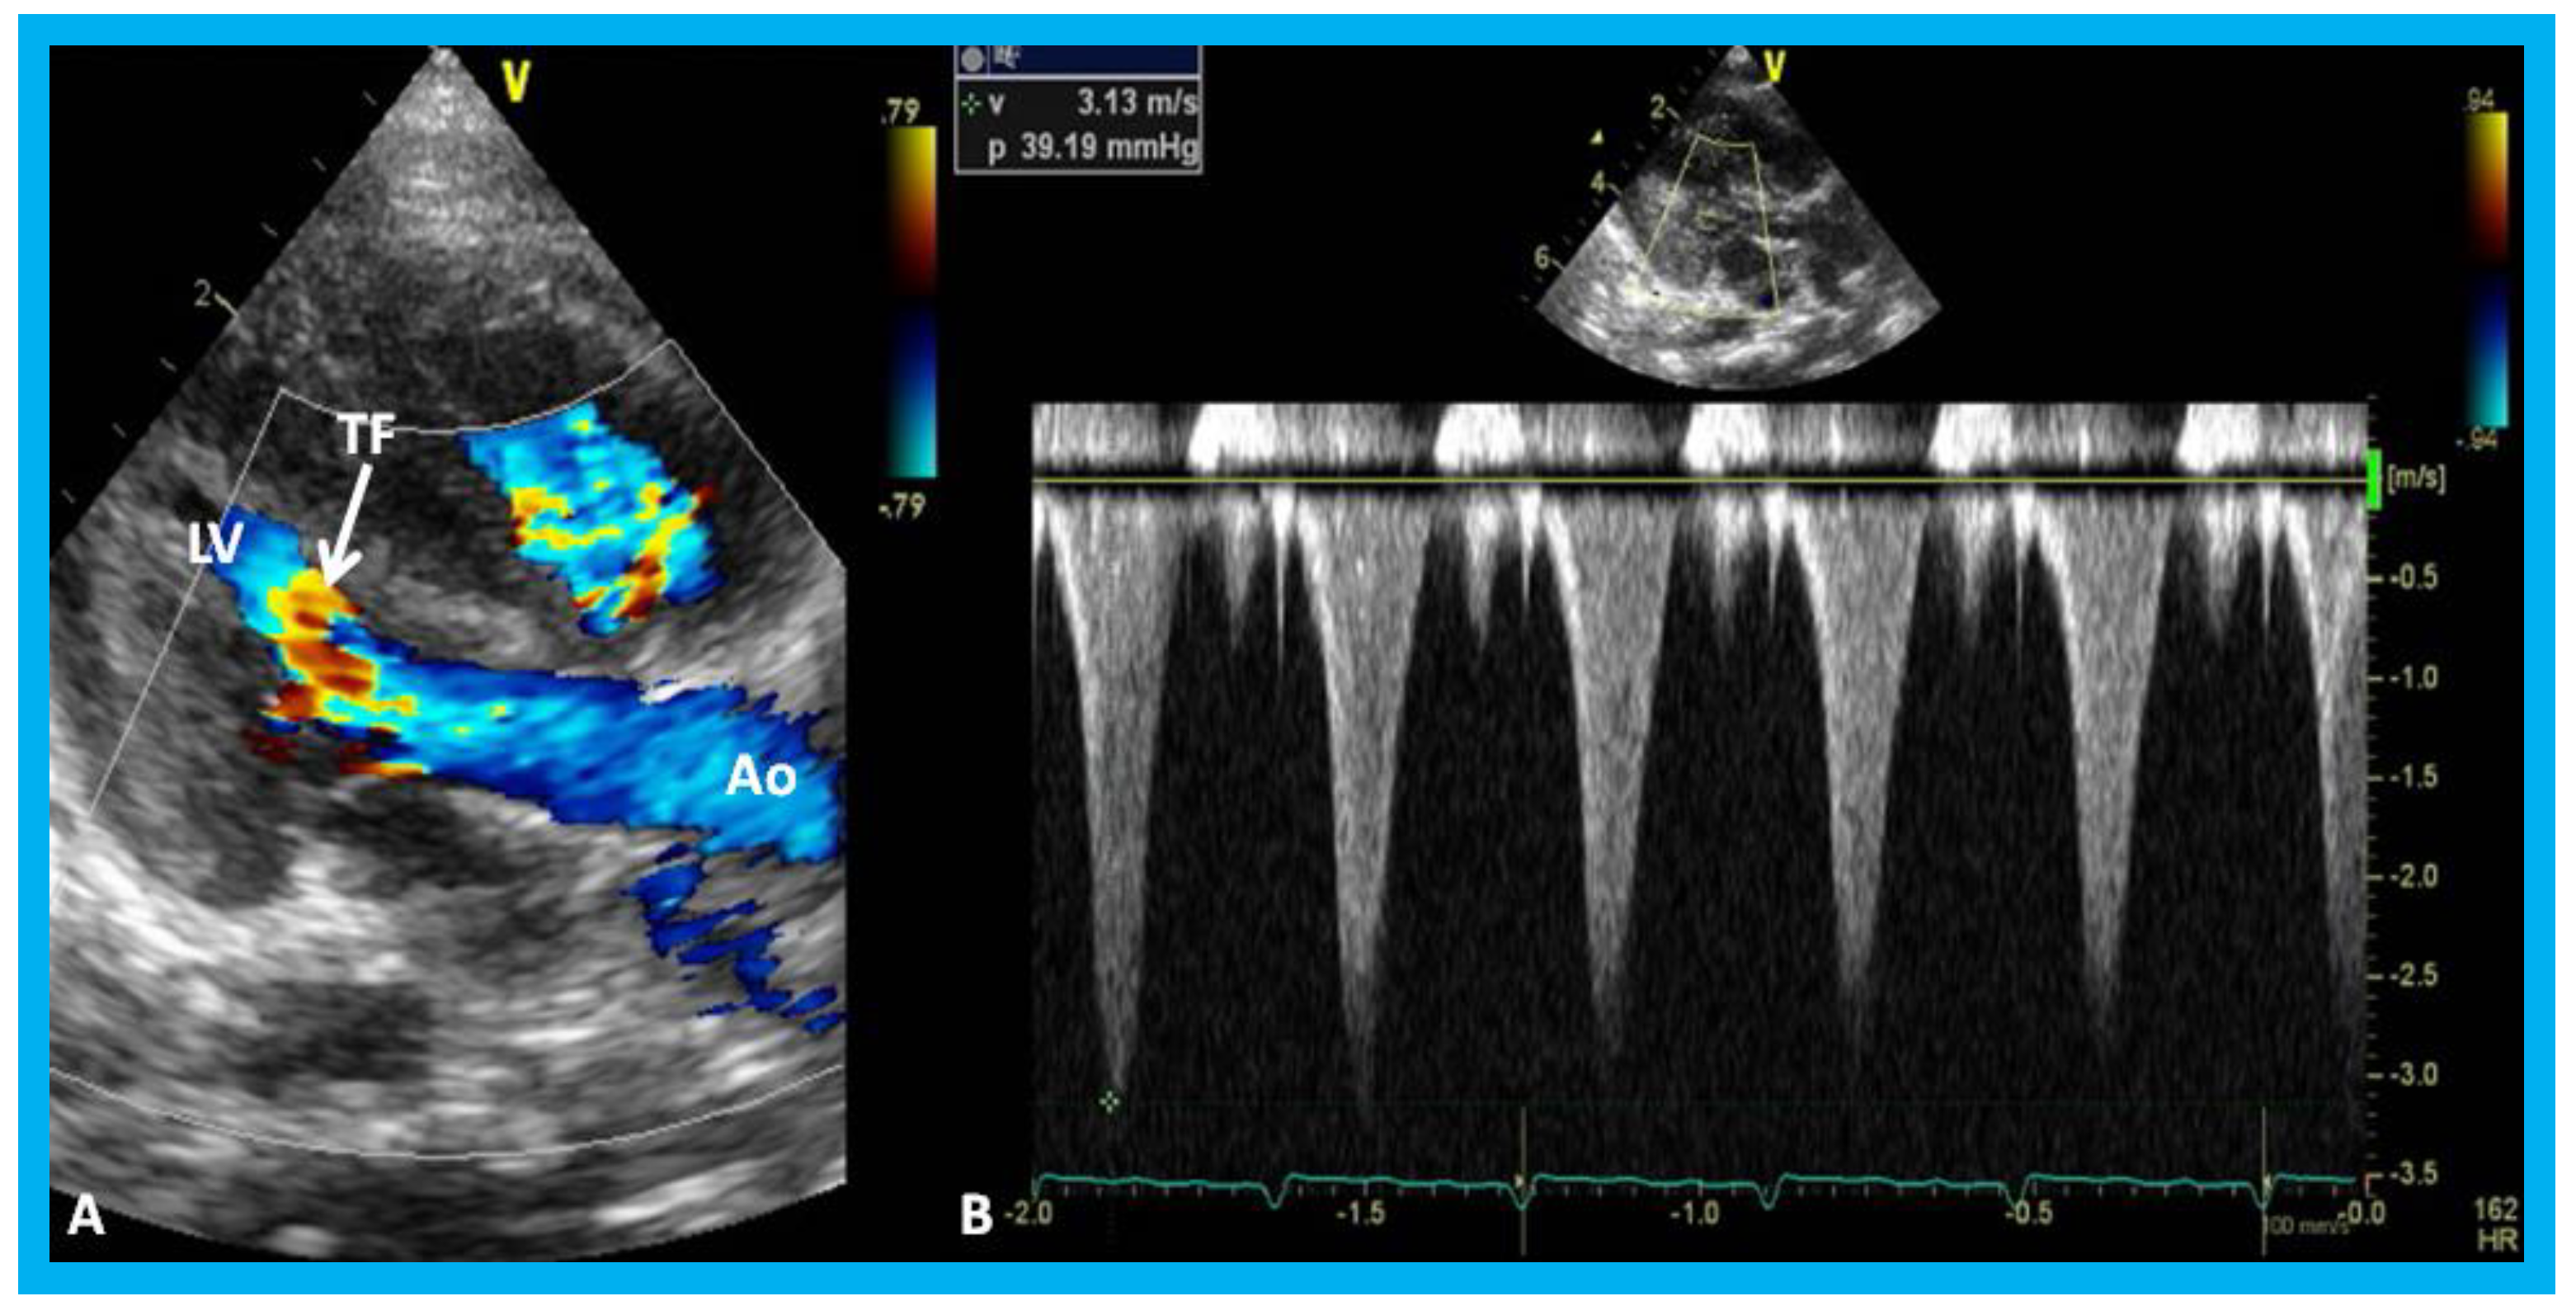

Figure 27. (A) Parasternal long axis, two-dimensional, and color-Doppler images demonstrating turbulent flow (TF) in the outflow tract of the left ventricle (LV) in an infant of a diabetic mother. (B) Continuous wave Doppler recording demonstrates a peak instantaneous gradient of 39 mmHg (see the insert in (B)): Note the triangular pattern of the Doppler recording indicative of subaortic obstruction. Ao, Aorta.